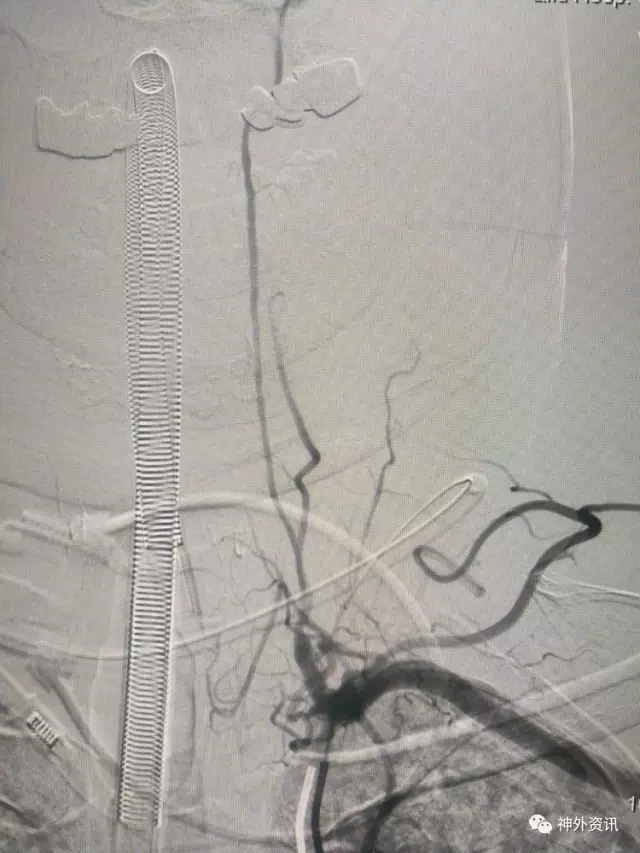

复合手术室一期造影,VA开口通畅,远端血管呈低灌性狭窄

L-VA颅内正侧位造影示pⅠCA显影好,正位示供血双侧,看来病人头晕的缺血症状该结束了

一月后CTA复查,左椎A开口无狭窄,远端管腔变粗,低灌注造成的狭窄明显改善,病人症状完全缓解